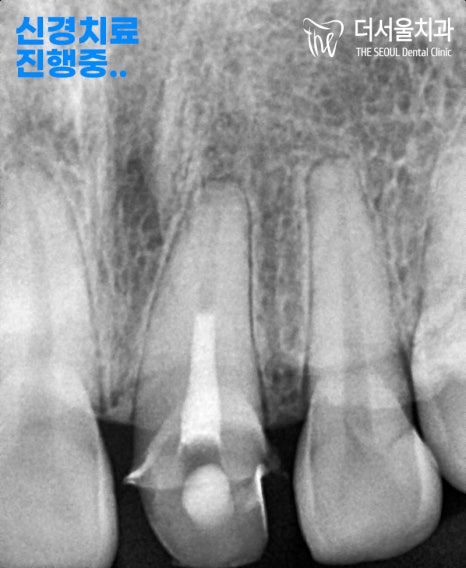

『근관치료 진행중…』

죽어버린 치수 조직을 제거하며,

충전 재료로 빈 공간을 채워드리는

과정을 진행합니다.

그 뒤에 크라운 보철을 씌울 수 있도록

프렙(Prep)이라는 단계를 시행합니다.

그 전에 태평동치과 에서

포스트라는 작업을 추천드렸습니다.

왜냐하면 크라운 보철을 씌웠을 때,

조금 더 오래 단단히 쓸 수 있도록

기반을 튼튼히 하는 과정을 거쳐야

사용 기간을 늘릴 수 있기 때문이죠.